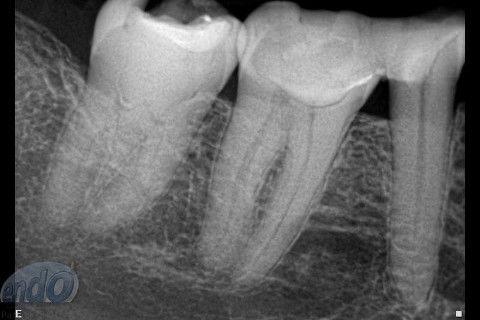

Seguem 3 casos clínicos realizados esta semana em uma cliente que está passando por um tratamento estético. O dente 47 apresentava calcificação da entradas dos canais radiculares, provavelmente, devido a uma pulpotomia realizada no passado. Desta forma, foi dedicada uma consulta de aproximadamente 2 horas para a realização deste procedimento. Os dente 45 e 46, por apresentarem canais radiculares com menor complexidade, foram tratados, simultaneamente, em sessão única com duração de aproximadamente 2 horas e 15 minutos.

Os três dentes foram tratados seguindo a técnica da FOP-UNICAMP, na qual é realizada patência e ampliação do forame apical. A instrumentação foi realizada com instrumentos rotatórios e como substância química auxiliar foram utilizados o ENDOGEL e o EDTA 17%. A irrigação ativa foi realizada com soro fisiológico. Os canais foram obturados com guta-percha e cimento PulpCanal Sealer, pela técnica de ondas contínuas de condensação.